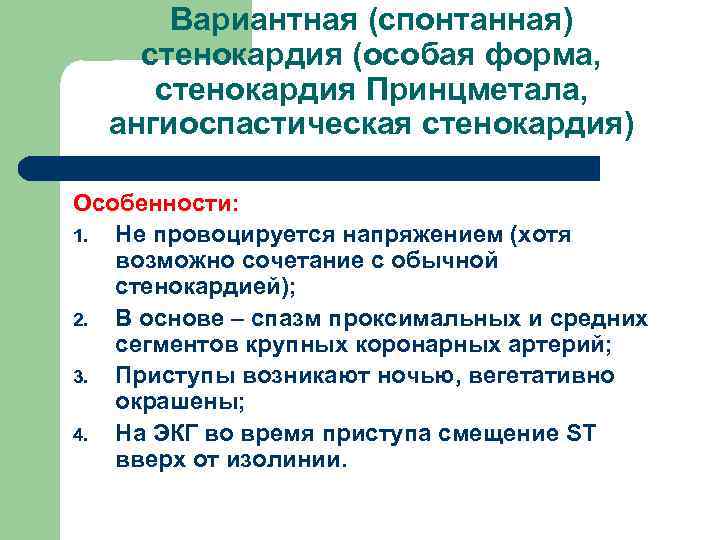

Вариантная (спонтанная) стенокардия (особая форма, стенокардия Принцметала, ангиоспастическая стенокардия) Особенности: 1. Не провоцируется напряжением (хотя возможно сочетание с обычной стенокардией); 2. В основе – спазм проксимальных и средних сегментов крупных коронарных артерий; 3. Приступы возникают ночью, вегетативно окрашены; 4. На ЭКГ во время приступа смещение ST вверх от изолинии.